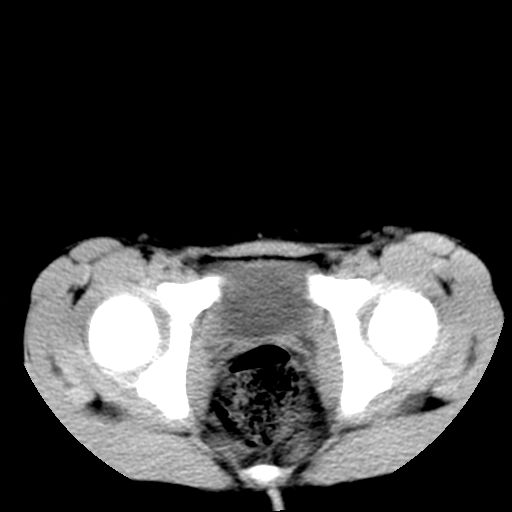

腹部好象未见异常。

腹部ct平扫未见明确异常

腹部ct平扫不能提示哪里有病变。